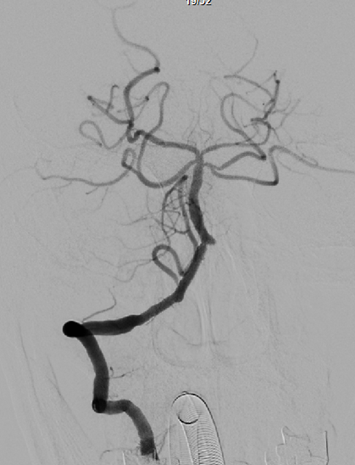

治疗中影像

病变情况分析:右桡动脉穿刺,置6F桡动脉鞘管,5F多功能导管在泥鳅导丝辅助下脑血管造影提示:右椎动脉V4段重度狭窄(约90%)。

导丝怎么扩【载药时代 球扩天下】NOVA DES®颅内药物洗脱支架在椎动脉颅内段重度狭窄的应用二例_https://www.jmylbn.com_新闻资讯_第31张

导丝怎么扩【载药时代 球扩天下】NOVA DES®颅内药物洗脱支架在椎动脉颅内段重度狭窄的应用二例_https://www.jmylbn.com_新闻资讯_第32张

泥鳅导丝携5F 115cm颅内支撑导管,至右椎动脉V2段。

在颅内支撑导管支撑下,将0.014'' 300cm微导丝,通过狭窄节段将其放置在基底动脉中段。将2.0mm*10mm球囊打起预扩狭窄部位,然后更换赛诺神畅 颅内药物洗脱支架NOVA DES® 2.5*10mm延微导丝顺利通过狭窄节段,再次造影见定位准确,缓慢扩张球囊释放支架。

导丝怎么扩【载药时代 球扩天下】NOVA DES®颅内药物洗脱支架在椎动脉颅内段重度狭窄的应用二例_https://www.jmylbn.com_新闻资讯_第33张

术后影像

术后即刻影像及患者术后情况:

造影见狭窄位置狭窄解除,支架贴壁良好,后循环各分支动脉显影良好。术后次日患者行走不稳情况明显改善,术后1月随访患者行走如常,未再发头晕。